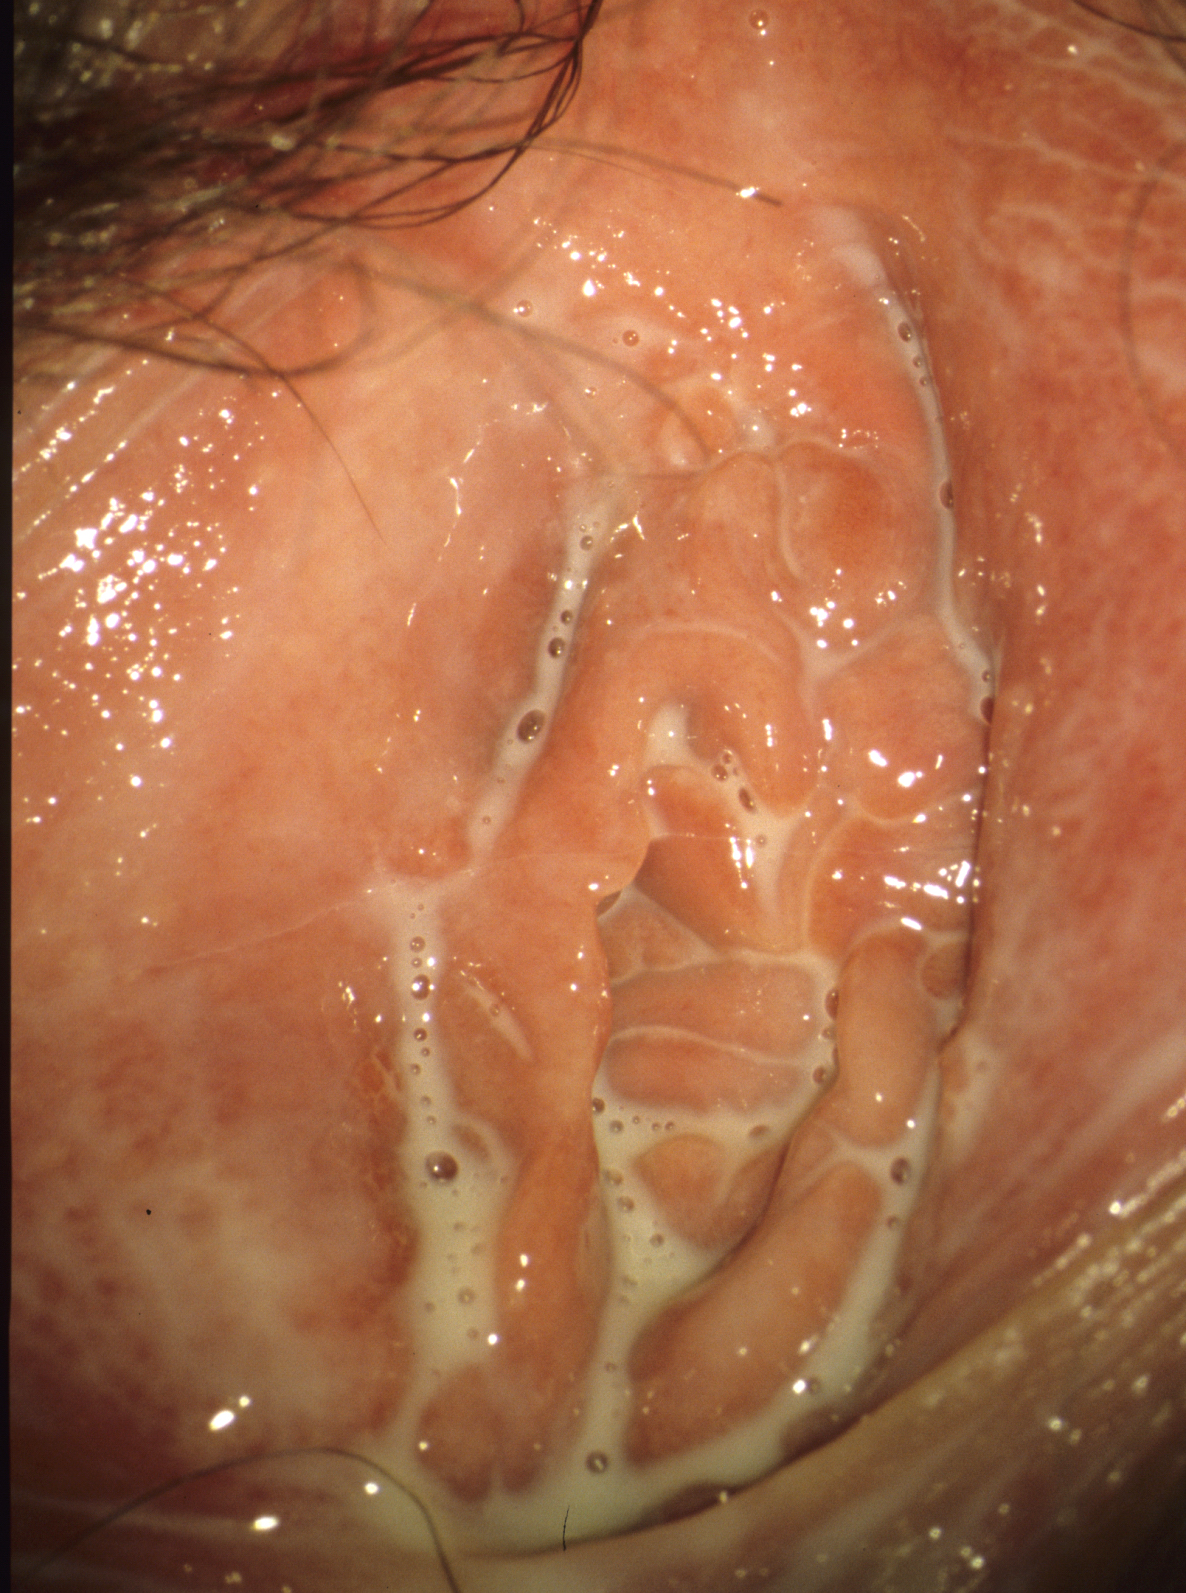

Lichen planus of the vulva

Its diagnosis on the vulva is difficult, since it is less frequent than the lichen sclerosus and its clinical picture is scarcely known. Lesions are white, reticular structures, which are almost recognizable only by colposcopy. This stage occurs many years before the better known late form, the Lichen planus erosivus, which is also called lichen ruber in the German-speaking world. At this stage, synechiae of the introitus are also possible with displacement of the urethral opening (Figure 4). The genital lichen planus is mostly accompanied by involvement of the oral cavity, facilitating the diagnosis. Otherwise, the diagnosis can be confirmed histologically. By early therapy (corticosteroid ointments), corresponding approximately to that of lichen sclerosus, the late stage can be largely avoided.

Figure 4: Lichen planus erosivus in a 50-year-old women (© Eiko Petersen)